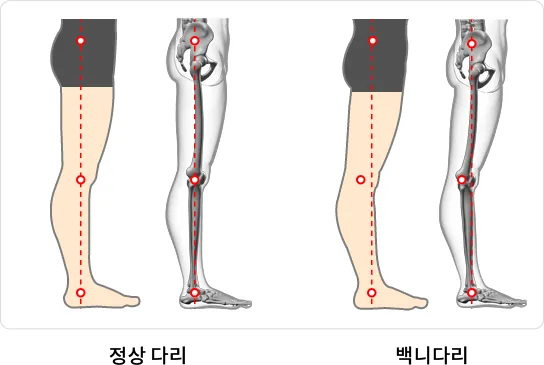

정면, 측면으로 분석하여 인체 근골격 모델로 현재의 신체 불균형 분석과 미래 체형을 예측

분석항목 : 거북목, 얼굴비대칭, 어깨불균형, 골반전·후방경사, 신체균형점, 내반슬(O다리), 외반슬(X다리), 반장슬(백니) 등